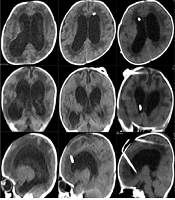

Complex Hydrocephalus in Children: Procedure of Surgical Management